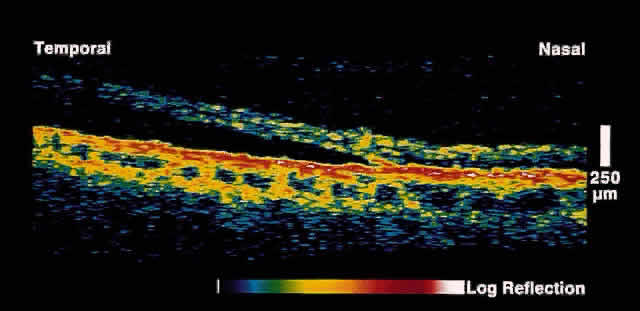

| Initial studies using postmortem eyes showed good correlation between OCT

images and histologic sections. Subsequent in vivo analysis demonstrated the ability of OCT to image the substructure of

the retina. Figure 1 shows an OCT image of a normal fovea and optic disc taken along the papillomacular

axis. Anatomic features such as the fovea, optic disc, and

retinal profile are evident. The vitreoretinal interface is noted by

the contrast between the nonreflective vitreous and the reflective surface

of the retina. The foveal center demonstrates normal retinal thinning

and has a characteristic pit to its contour. The optic disc demonstrates

normal nerve head contour and cupping. The retinal nerve fiber

layer, inner plexiform layer, outer plexiform layer, photoreceptor layer, choroid, and

sclera are all well delineated. The posterior aspect of the neurosensory retina is bounded in the OCT images by a highly reflective red layer about 70 microns thick that represents the choriocapillaris and retinal pigment epithelium (RPE) layer. In vivo choriocapillaris thickness by OCT is greater than that of histologic sections because of postmortem blood depletion and artifacts in tissue processing. The high contrast between the choriocapillaris/RPE layer and the neural retina in OCT images provides a useful boundary for use in measurements of retinal thickness. Retinal blood vessels are evident in OCT images by their shadowing of deeper retinal structures. The region just anterior to the choriocapillaris/RPE layer is typically weakly reflective and corresponds to the photoreceptor layer. The highly reflective red layer at the inner margin of the retina corresponds to the nerve fiber layer. In the OCT image taken along the papillomacular axis (see Fig. 1), the thickness of the nerve fiber layer increases from the fovea to the optic disc. Circular tomographs taken around the disc demonstrate modulations in thickness consistent with the superotemporal and inferotemporal bundling of the nerve fibers. Because retinal detail is so exquisitely imaged by OCT, this imaging modality can be applied to a large number of clinical entities. |